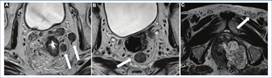

Estadificación del cáncer de recto inferior

Poder describir el compromiso de las diferentes partes del esfínter anal es determinante para la elección de tratamiento quirúrgico por parte del cirujano. Aquellos tumores de recto inferior sin compromiso esfinteriano son factibles de cirugía de ETM con conservación del esfínter, mientras que el compromiso de cualquiera de los elementos que lo conforman es determinante de cirugía con resección total o parcial del esfínter. Por dicha razón, debe analizarse la extensión lateral tumoral determinando: a) la relación de la lesión con los músculos elevadores del ano; b) la presencia/ausencia de componente tumoral en el espacio interesfinteriano; c) la presencia/ausencia de invasión del esfínter anal externo, y d) determinar la existencia de invasión a órganos vecinos. Teniendo como base esta información, se desarrolló una estadificación que complementa el TNM en los casos de compromiso del recto inferior 8,14 (Figs. 14 y 15).